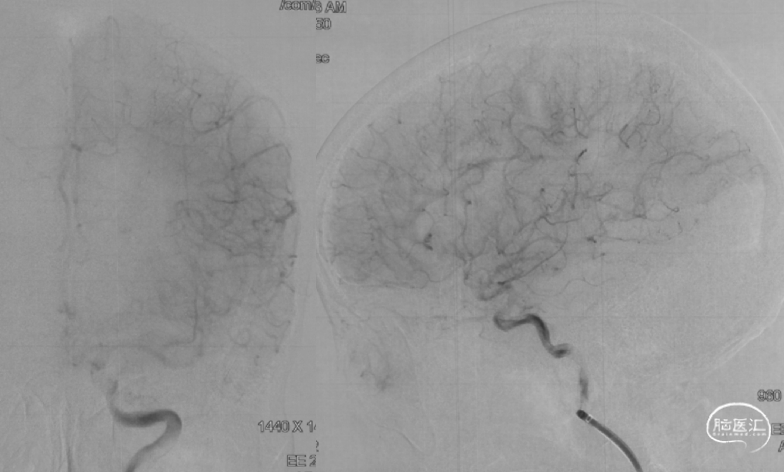

抽吸一次,达到eTICI 2C再通。

术后即刻患者NIHSS评分3分,24h NIHSS评分0分。